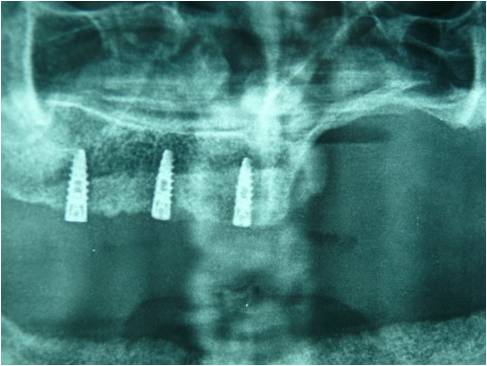

Chirurgia Oro-Mascellare per riabilitazioni protesiche post oncologiche

I pazienti che per motivi oncologici o per esito di osteonecrosi per uso di farmaci della categoria bifosfonati (in uso nelle gravi forme di osteoporosi o nel trattamento coadiuvante delle metastasi ossee)hanno subito gravi demolizioni dei mascellari e conseguente perdita della funzionalità masticatoria necessitano di ricostruzione e rifunzionalizzazione dell'apparato masticatorio con ricostruzione dell'osso mandibolare o del mascellare superiore attraverso innesti di osso , di lembi mucosi e/o muscolari di vicinanza ed a volte di implantologia preprotesica con impianti zigomatici , pterigoidei o convenzionali , tutto cio'con il fine di ripristinare una corretta funzione ma anche una auspicabile vita di relazione.

![]() | ![]() | ![]() | ![]() |